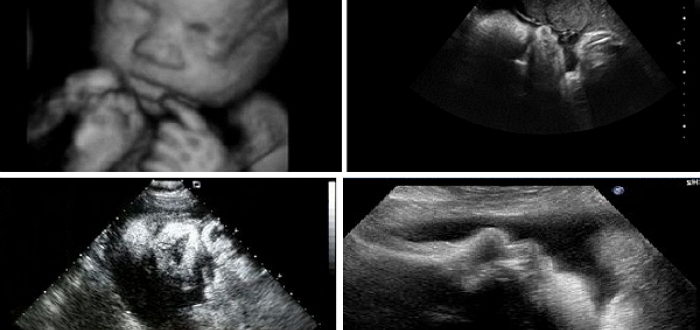

Вредно ли УЗИ на 38 неделе беременности

Как делают УЗИ на 38 неделе беременности: показания, подготовка, расшифровка На сроке 38 недель женщина уже полностью готова к родам. Ее малыш может появиться в любой момент. Некоторые…